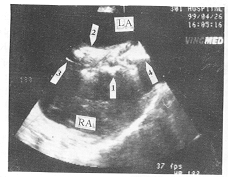

图2 TEE术中引导Amplatzer ASD封堵器关闭ASD。 左房伞、 腰部及右房伞已展开, 卡于ASD处。 LA左房, RA右房。 箭头1: 右房伞, 箭头2: 左房伞, 箭头3 4: 房间隔

二、 术后立即、 24h、 1月及3月超声心动图检查, 16例患者封堵器位置合适、 稳定, 均无残余分流, 未影响周围瓣膜功能及静脉回流(图2)。